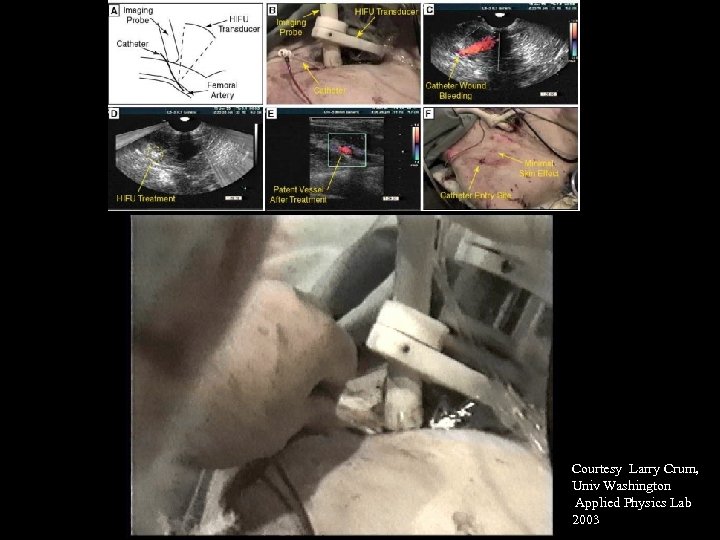

Courtesy Larry Crum, Univ Washington Applied Physics Lab 2003

Courtesy Larry Crum, Univ Washington Applied Physics Lab 2003